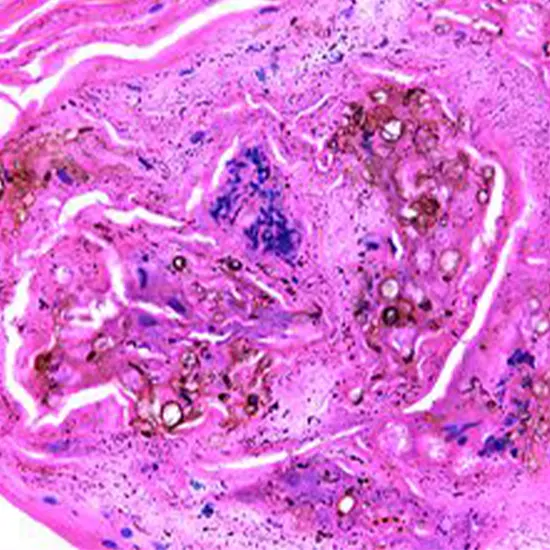

Diagnosis of chromoblastomycosis is usually confirmed through microscopic examination of skin scrapings or biopsy samples, which reveal characteristic brown, thick-walled, spherical or muriform (multicellular) fungal structures. Fungal culture and molecular methods may also be used for identification of the causative fungi.